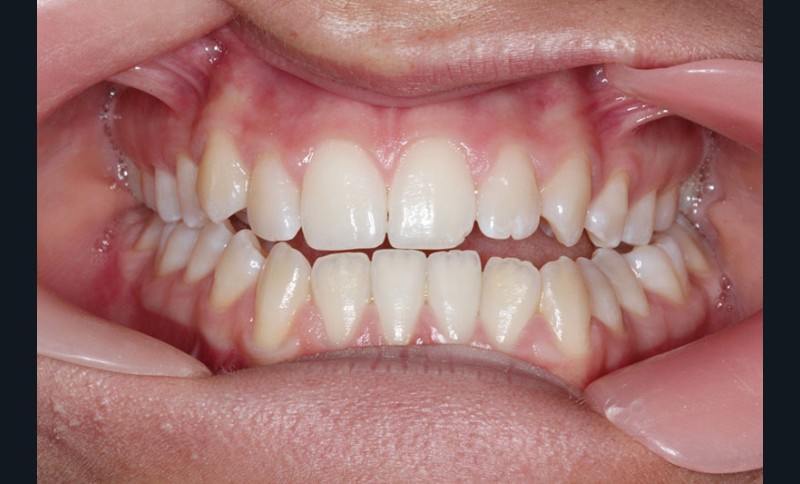

Cas clinique n° 2 : Motion Classe III

Nous sommes en présence d’une patiente en fin de croissance faciale, âgée de 16 ans. Elle présente une classe III dentaire et squelettique associée à une asymétrie faciale de type latérognathie mandibulaire avec déviation des points interincisifs et déviation du menton vers la gauche.

Pour des raisons personnelles, la patiente refuse un protocole orthodontico-chirurgical. Nous optons pour une réduction de la classe III par compensations dento-alvéolaires car la progénie n’est pas très importante et nous estimons que le résultat dentaire, squelettique et facial peut être cohérent. Un système « Motion Classe III Carriere » va être utilisé suivi d’un appareillage multibague « Carriere SLX ».